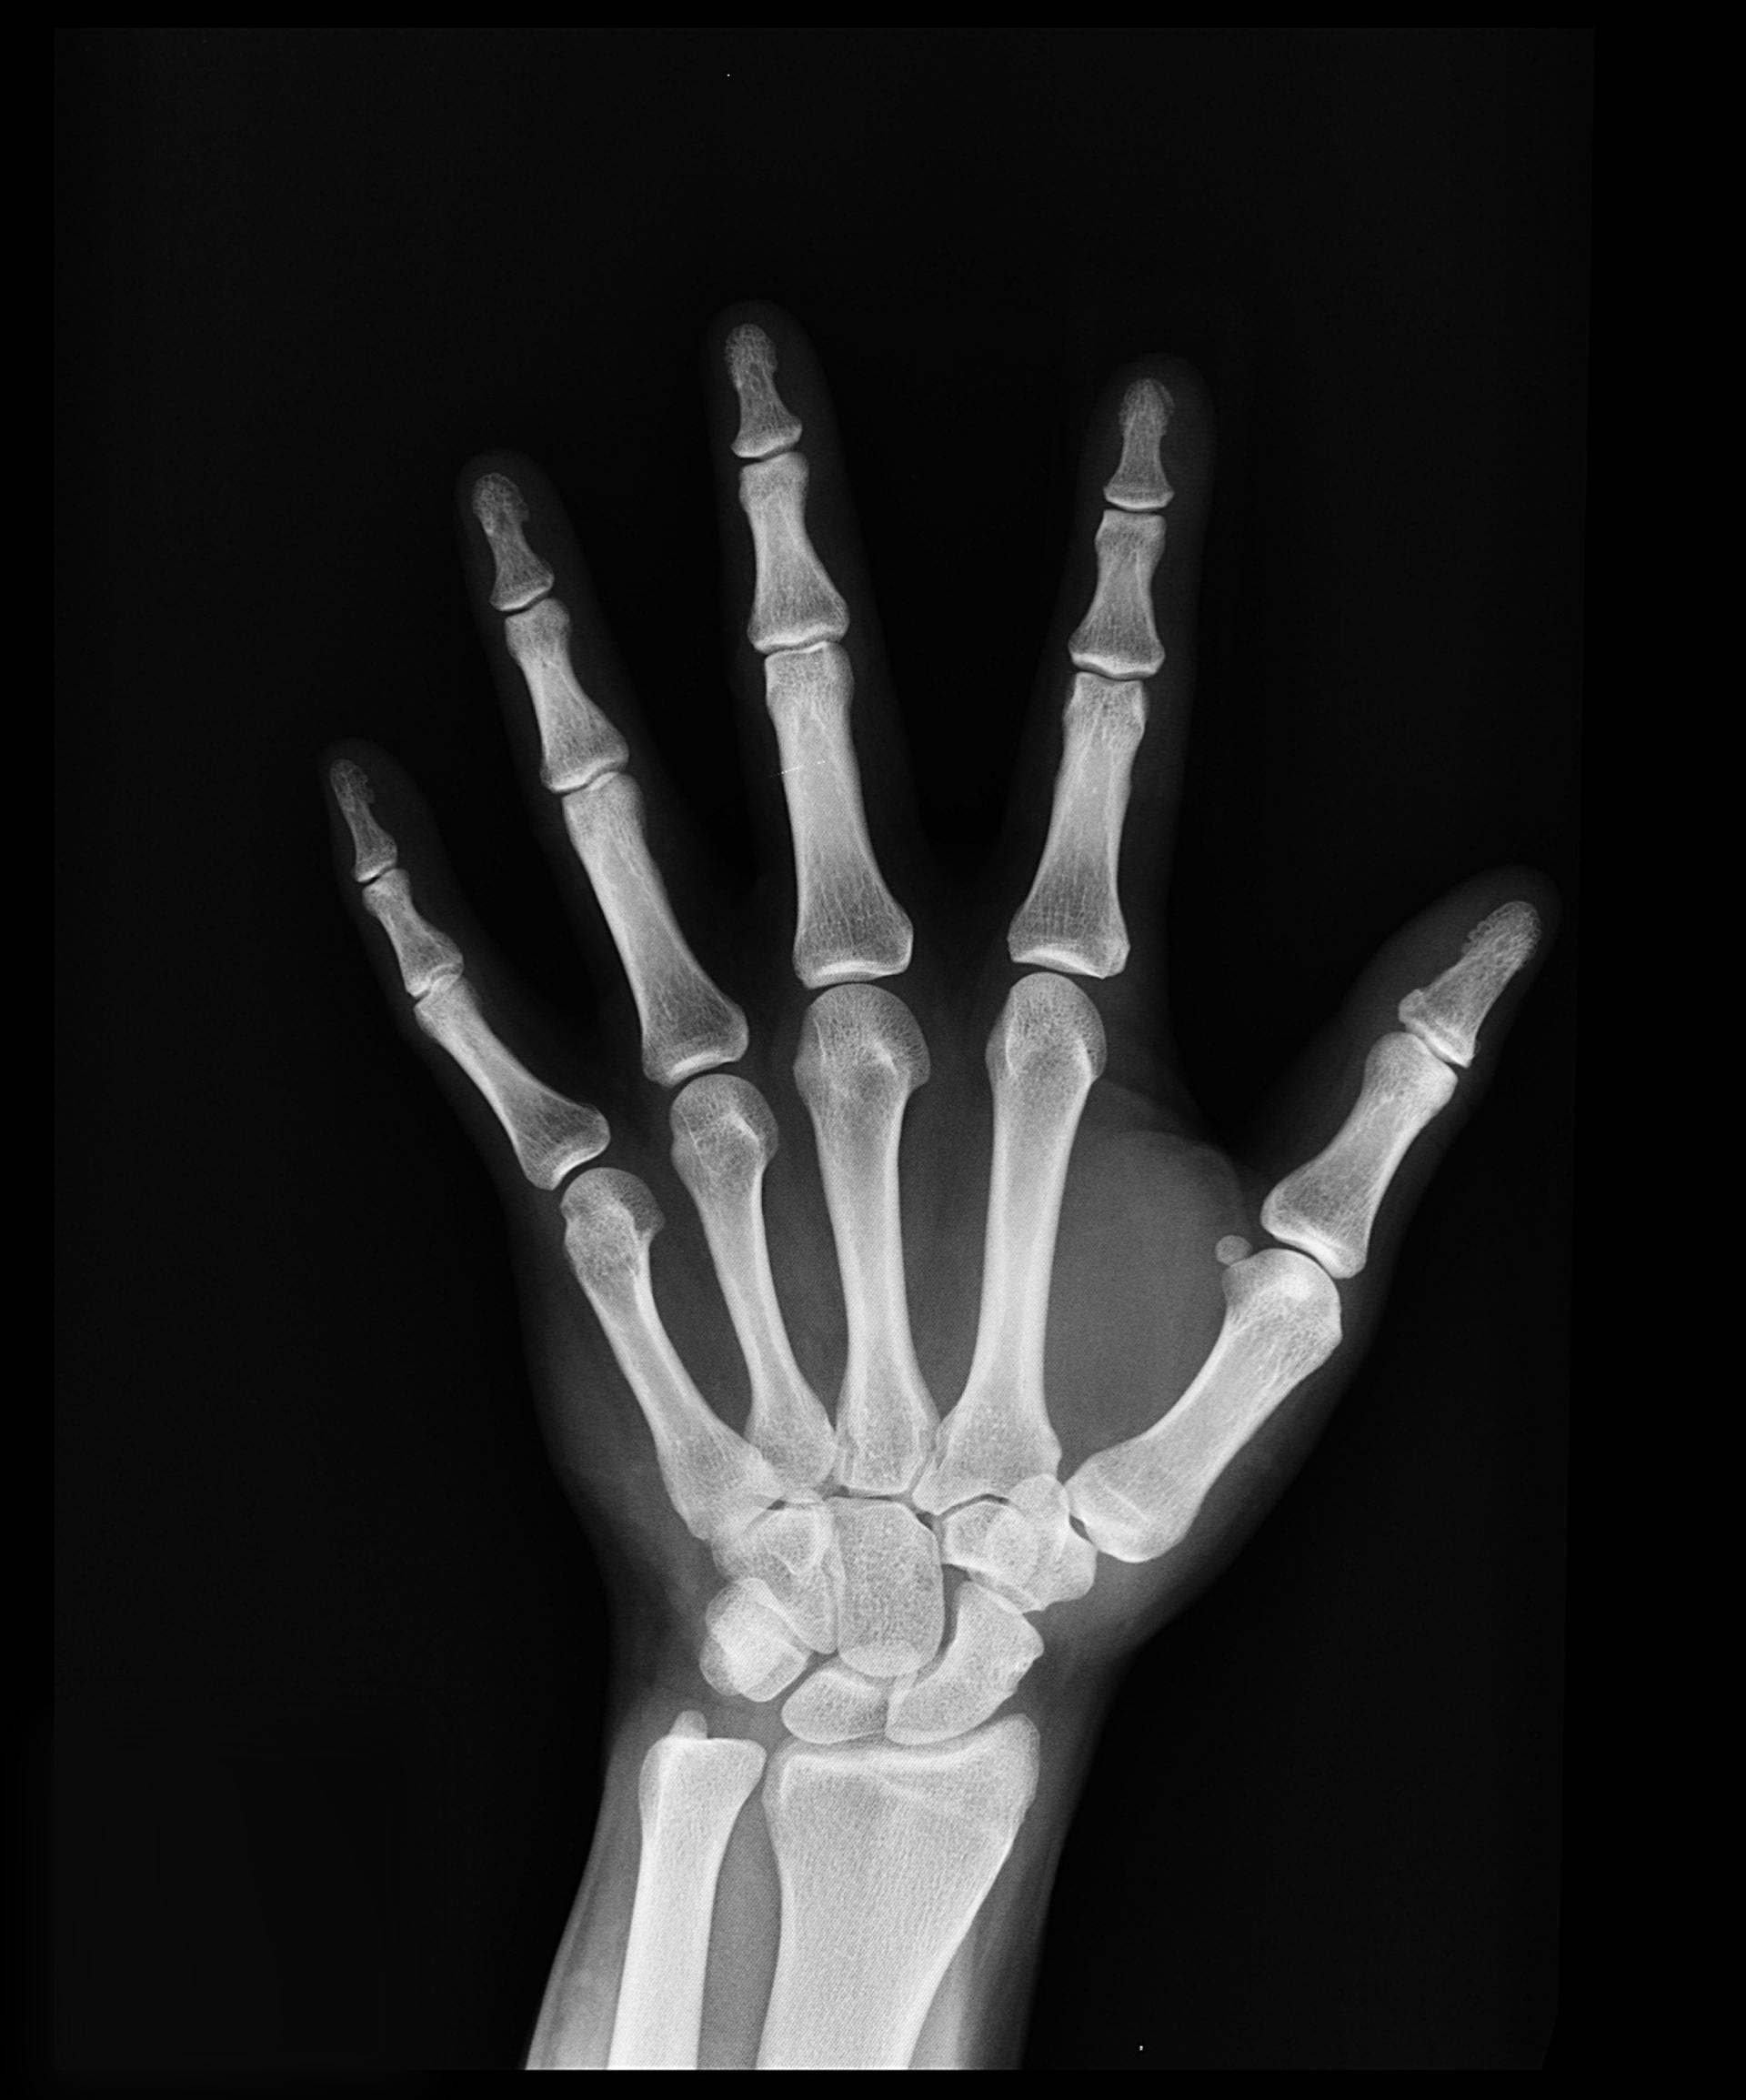

1) 골다공증과 골연화증 위험

비타민D가 부족하면 칼슘 흡수율이 낮아지고, 그 결과로 뼈가 약해질 수 있습니다.

성인에서는 골연화증, 노년기에는 골다공증의 위험이 높아집니다.

**골다공증 유병률: 65세 이상 여성 기준 약 37.3% (2022년 국민건강영양조사, 질병관리청)

특히 여성 갱년기 이후라면 비타민D와 칼슘 모두 적극적으로 챙길 필요가 있습니다.

2) 근육 약화와 낙상 위험 증가

근육세포에도 비타민D 수용체가 존재합니다.

부족하면 근력 저하로 인해 평형 감각이 떨어지고 낙상 사고 위험이 높아지죠.

노년층에게 특히 중요한 이유입니다.

** 65세 이상 낙상으로 인한 골절 사고 발생률: 약 25.5% (2021년 국민건강보험공단)